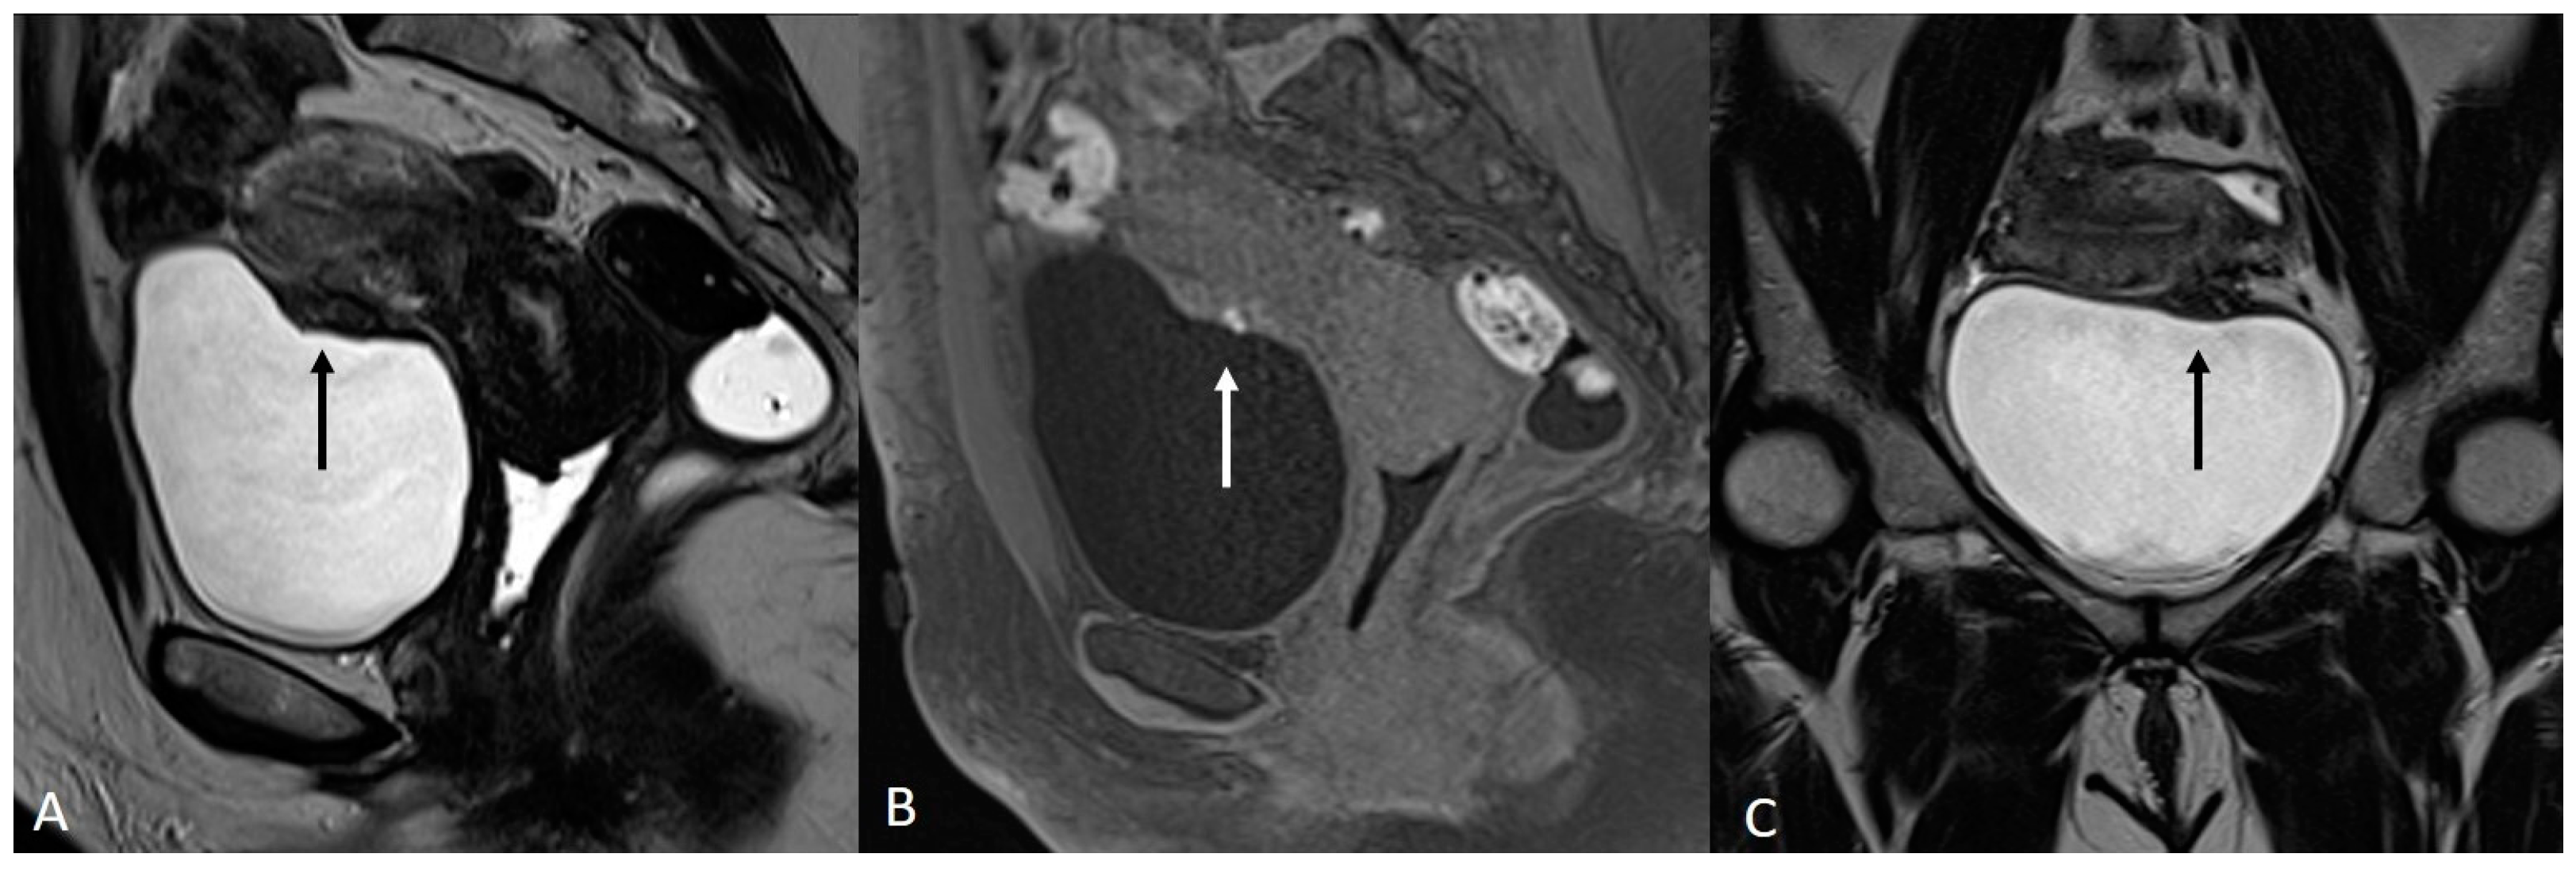

On an MRI, endometriomas appear as cystic lesions with different signal characteristics according to the age of the blood and the type of hemoglobin present.

Generally, they appear hyperintense on fat-suppressed T1WI and T1WI (Figure 7 and Figure 8). The hyperintensity on fat-suppressed T1WI helps differentiate endometriomas from dermoid cyst and teratoma, which usually contain fat [51]. On T2WI, a variable signal can be obtained: a hypointense signal can affect variable portions of the cyst, sometimes also presenting a stratification, until a complete loss of the signal. This is called the shading sign and is correlated to the different state of hemoglobin degradation [52] (Figure 8). The T2 dark spot sign refers to hypointense spots in the wall of the cyst due to the presence of macrophages (Figure 9).

Figure 7.

Ovarian endometrioma in a 37-year-old female. (A) Axial T1WI; (B) Axial fat-suppressed T1WI. Typical aspect of an ovarian endometrioma (white arrows).

Figure 8.

Right tubo-ovarian endometriosis in a 25-year-old female patient with reported localized abdominal pain in the right iliac fossa, which increases intensity during the menstrual cycle. (A) Axial T2WI; (B) Axial fat-suppressed T1WI. Enlarged right adnexal cyst with incomplete septa denoting dilated tube (white arrows). The cystic content shows low signal intensity on T2WI and high signal intensity on fat-suppressed T1WI, consistent with hemorrhagic fluid.